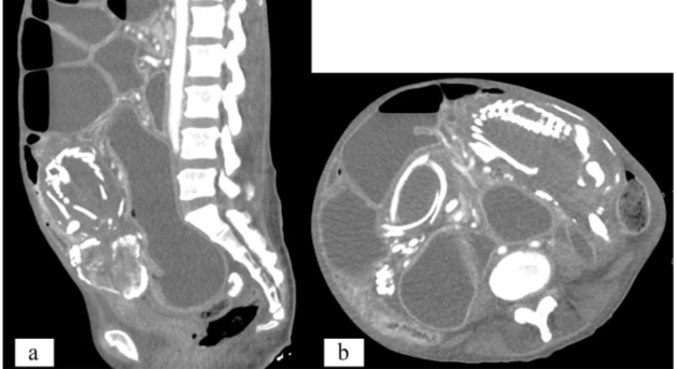

Exames mostram estruturas fetais ósseas

Uma semana após sua consulta inicial em solo norte-americano, a refugiada se apresentou no departamento de emergência para avaliação de náuseas e vômitos intratáveis. Uma radiografia abdominal mostrou esqueleto fetal e padrão inespecífico de gases intestinais com leve distensão intestinal, além de obstrução local. Ela foi internada durante a noite para observação clínica.